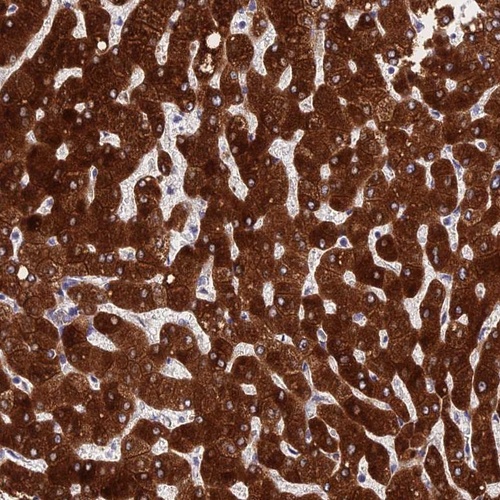

Immunohistochemical staining of human liver shows strong cytoplasmic positivity in hepatocytes.